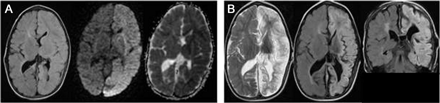

解决破裂后抑制EEG成为严重抑制整个左半球。MRI大脑在医院第五天显示限制扩散与表观扩散系数关联在左半球(图)。这下个月进步更普遍的信号异常的整个左半球和体积损失可能符合分散皮质坏死(图、B)。日常电解质及CSF分析演讲的时候都在正常范围内。

MRI大脑做在医院一天5显示fluid-attenuated反转恢复(天赋)(左),diffusion-weighted成像(中间)和表观扩散系数(右)在左半球(A)信号异常。这些异常并不符合任何血管领土。这下个月进步更普遍的信号异常的整个左半球和体积损失可能符合分散皮质坏死出现在t2加权(左)和天赋轴向(中间)和冠状图像(右)(B)。